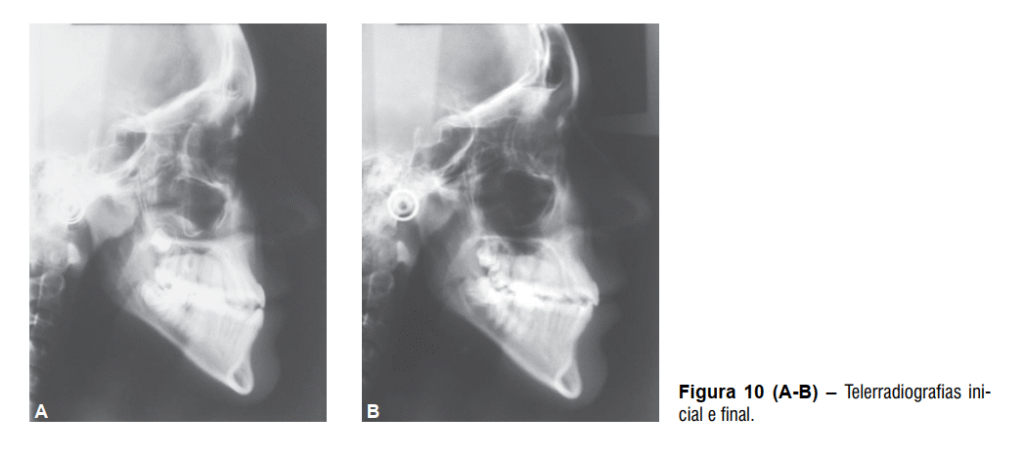

Após a remoção do aparelho fixo foi instalada como contenção uma placa de Hawley superior, 3×3 inferior e uso noturno de mentoneira com finalidade de restringir o crescimento mandibular. O tratamento proposto possibilitou a correção da discrepância transversal e da relação anteroposterior de forma satisfatória, melhorando o perímetro do arco e obtendo-se uma relação molar de Classe I (Figura 8 A-E), além da melhora significativa do perfil facial e estética mais agradável (Figura 9 A-B). As telerradiografias inicial e final mostram a melhora da relação entre as bases ósseas (Figura 10) juntamente com a sobreposição dos cefalogramas (Figura 11).

O componente esquelético da maxila não apresentou grandes alterações, entretanto, a mandíbula teve significante crescimento representado pela variável CoGn. Também houve suave aumento das variáveis que representam o padrão da face no sentido vertical, com destaque para a alteração sofrida pela variável AFAI, que teve aumento de 4,1 mm (Tabela 1).

O componente dentoalveolar da maxila apresentou maiores alterações, assim como já era esperado. Os incisivos superiores apresentaram vestibularização e protrusão enquanto os molares superiores apresentaram mesialização com angulação da sua coroa para a mesial (Tabela 1). O componente dentoalveolar inferior apresentou suaves alterações, principalmente em relação à extrusão sofrida pelos incisivos inferiores (Tabela 1).

Na relação entre os dentes superiores e inferiores houve grande melhora representada pelas variáveis:

relação molar, trespasse horizontal e trespasse vertical (Tabela 1), assim como houve visível melhora em relação ao perfil facial, que ao final do tratamento se apresentava menos côncavo (Tabela 1)